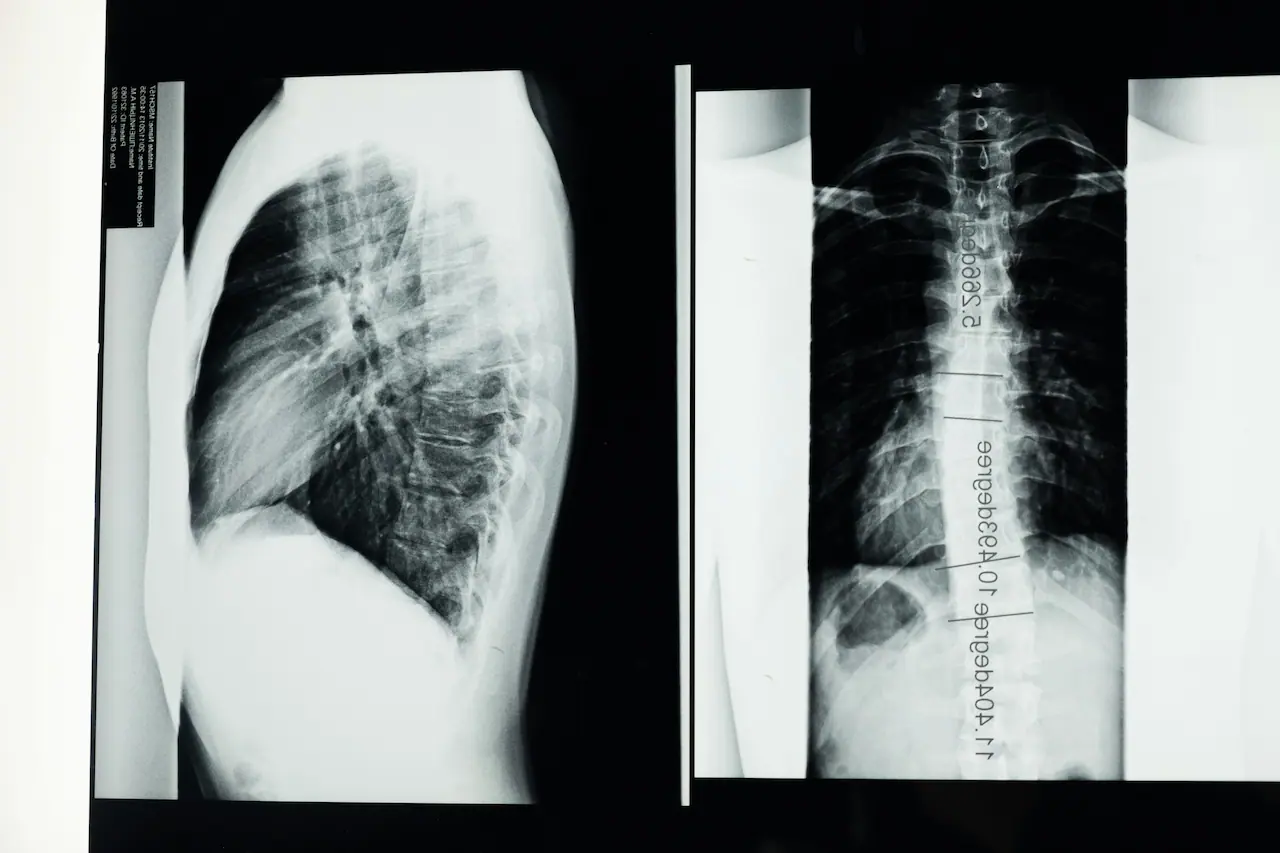

Scoliosis is a three‑dimensional curve of the spine, defined on X‑ray as a sideways curvature of at least 10 degrees. In adults, scoliosis may be a curve that began in adolescence and progressed, or it may develop later in life due to age‑related changes such as disc degeneration or arthritis (degenerative scoliosis).

Many people with mild scoliosis have few or no symptoms, although they may notice uneven shoulders, a visible rib prominence, or their clothing sitting unevenly. When scoliosis is more pronounced, some adults experience back pain, muscular fatigue, leg symptoms or reduced tolerance for standing and walking.

Kyphosis describes the natural forward curve of the upper back (thoracic spine). When this curve becomes exaggerated it may be called hyperkyphosis and may be noticed as a rounded or hunched posture.

Structural kyphosis: The vertebrae or discs are altered, such as in Scheuermann’s disease or with osteoporotic compression fractures, and the curve is more rigid. Structural kyphosis can sometimes cause pain, stiffness and functional difficulties, particularly in more severe cases.